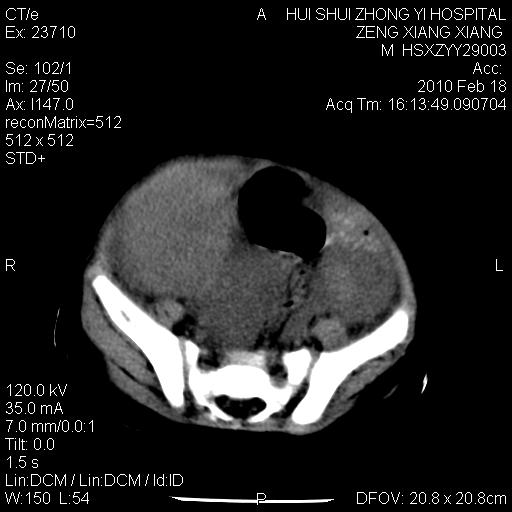

标题: PED3106:男,2岁,腹胀1月。 [打印本页]

标题: PED3106:男,2岁,腹胀1月。

定位腹膜后,肾上腺来源;

定性:恶性神经源性,肾上腺神经节母细胞瘤可能性大。

鉴别:肝母、肾母、肝脏中胚层错构瘤。

依据:年龄、有钙化,肾脏及肝脏受压移位。

肝母细胞瘤可能性大,右肾形态大体可见,不支持肾母细胞瘤,右肾移位不明显,肾上腺神经母细胞瘤可能性不大。